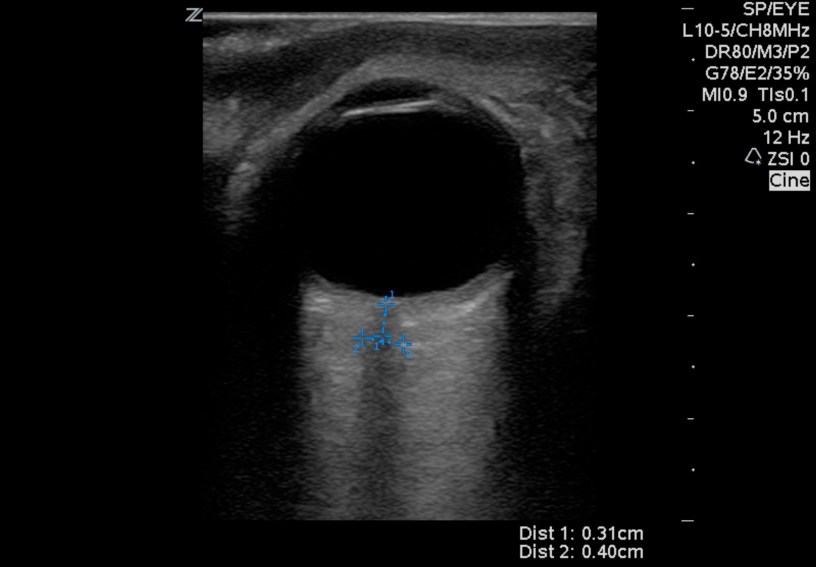

Two awesome medical students Nick and Max tackle optic nerve sheath diameter or ONSD in this months NUSIG journal club podcast. Is it useful? How do you peform the exam? What’s the sensitivty to rule out elevated intracranial pressure?

National #Ultrasound Interest Group Journal Club – Topic ONSD #pocus #foamed #foamus